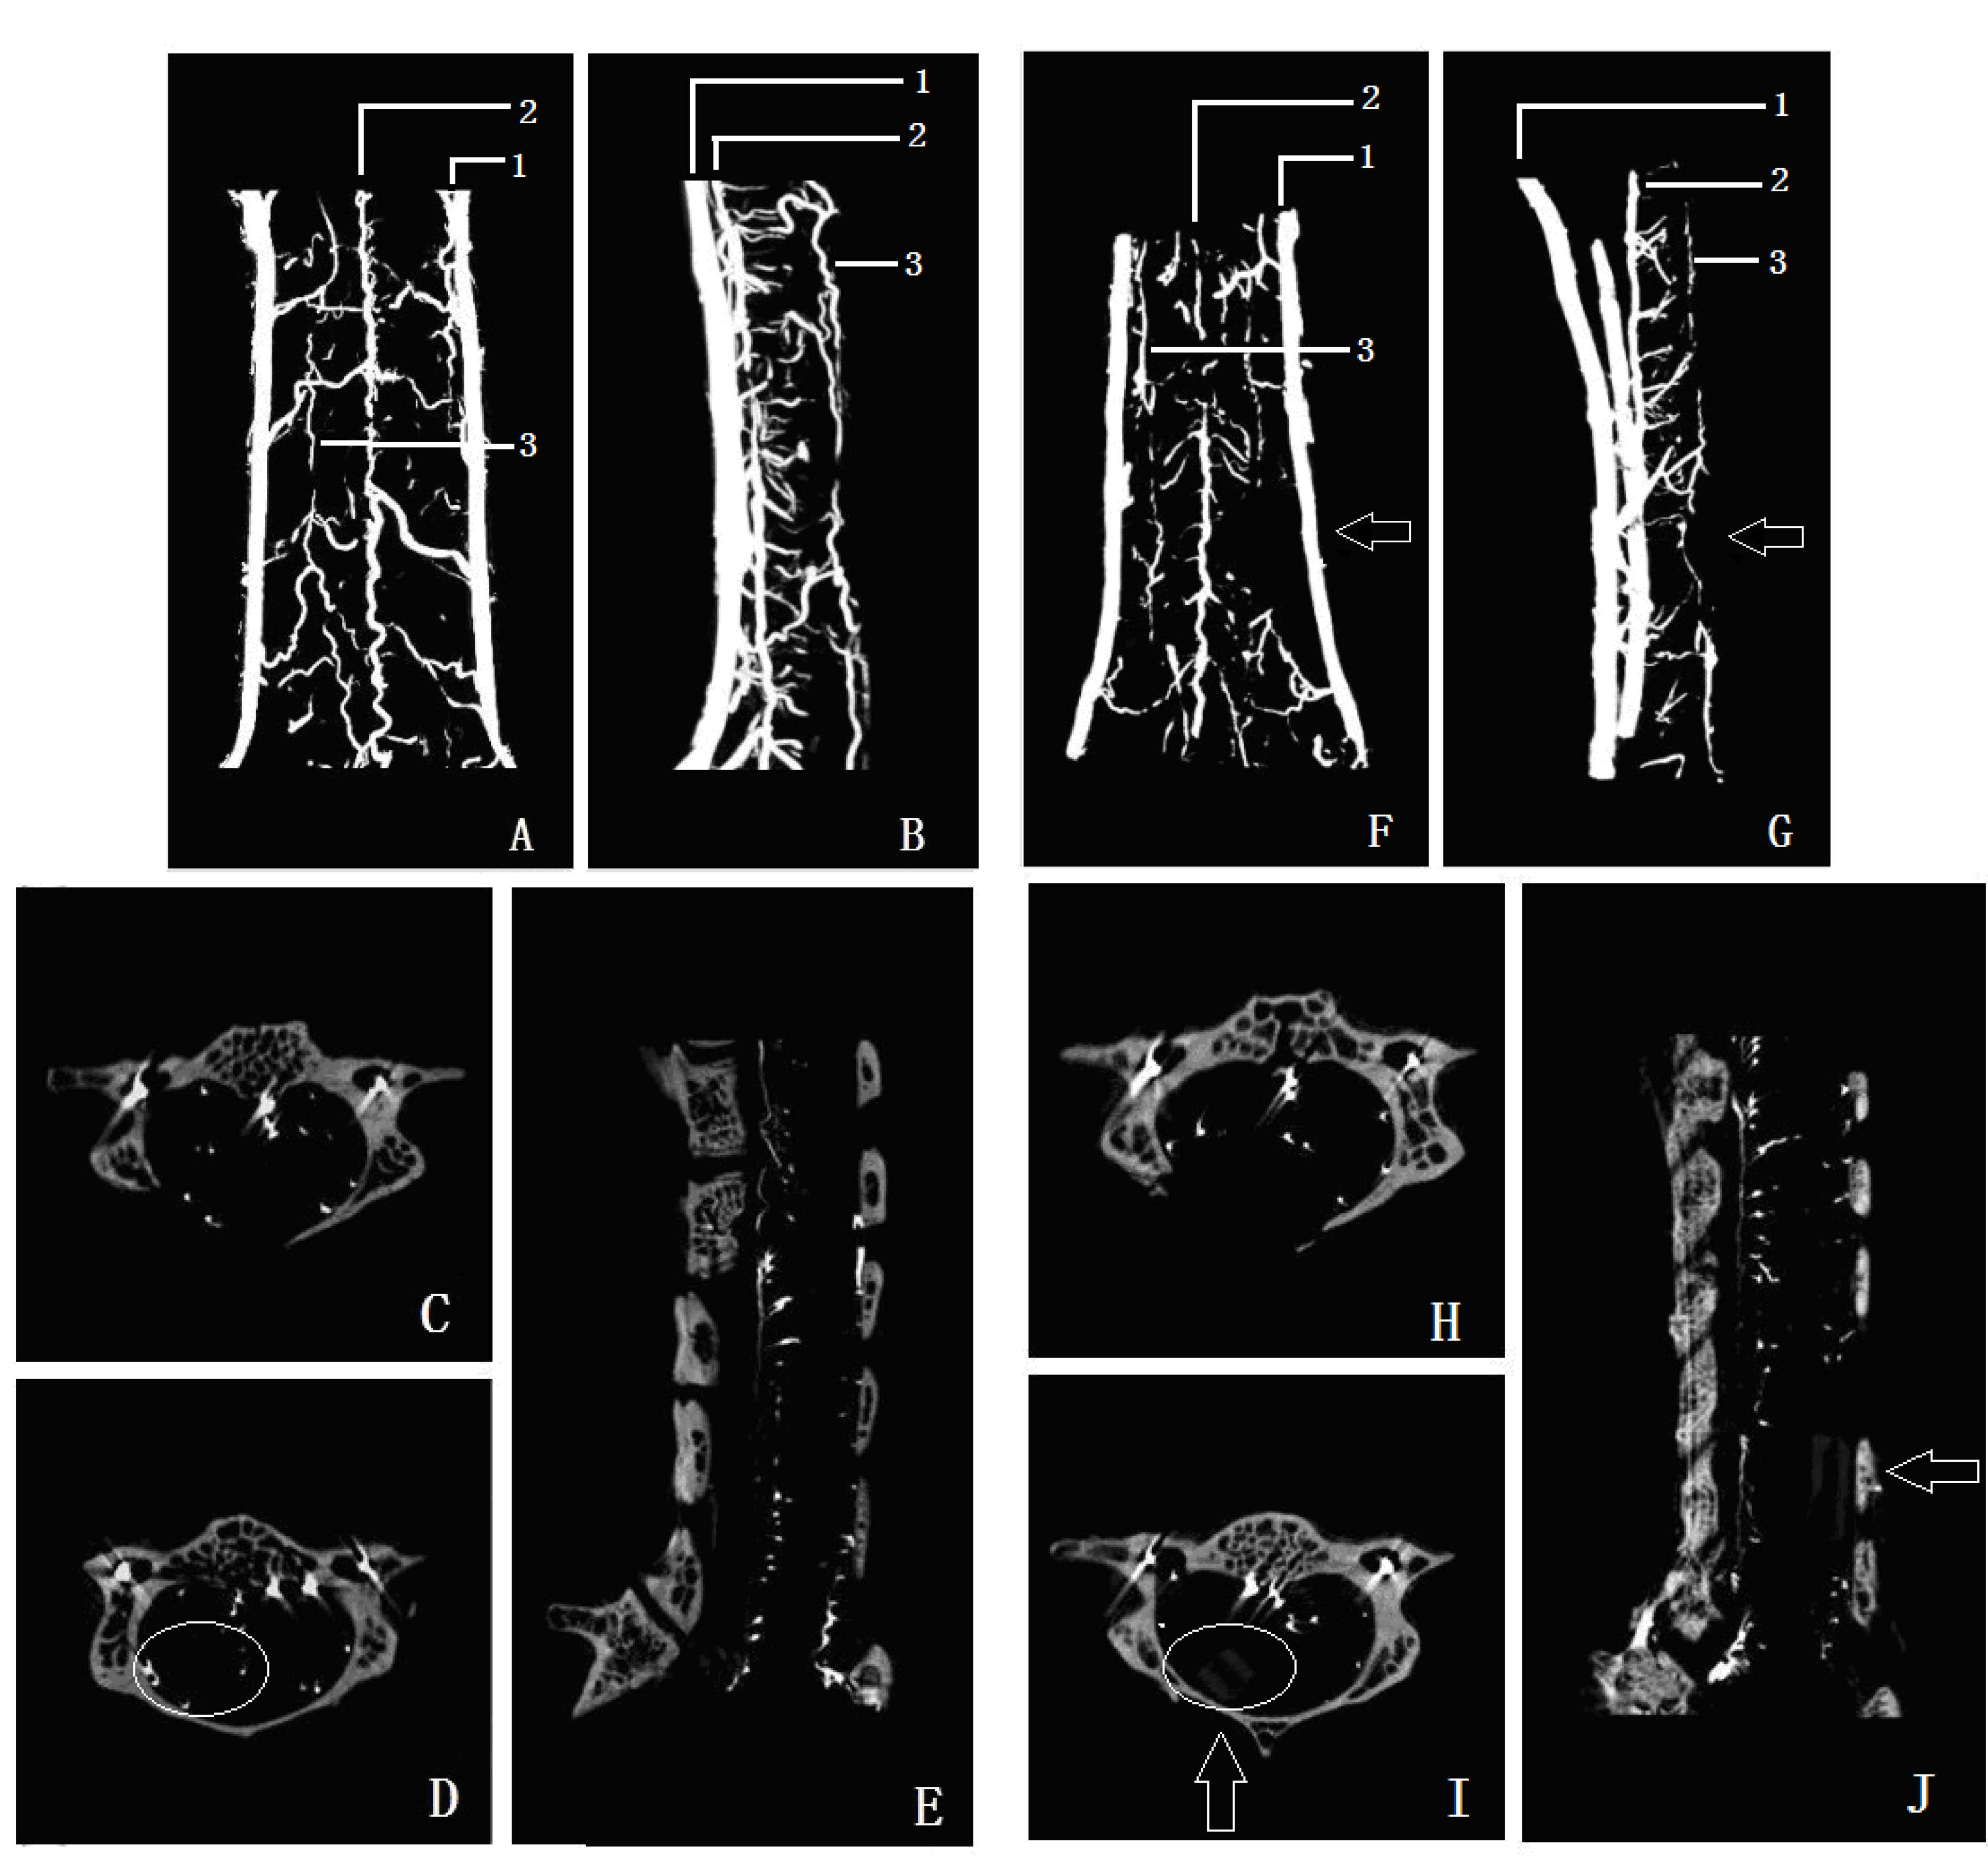

As shown in Figure 5, the contrast micro-CT of the microvascular system was presented in 3D coronal view (Figure 5A,F), in 3D sagittal view (Figure 5B,G), in 2D sagittal view (Figure 5E,J), and in cross section view (Figure 5C,D,H,J).To compare the microvascular change in the compression area, a 2D cross section in the compressor inserting site and the compression site were shown in Figure 5H,I, 2D sagittal section in sham group and compression group were showed in Figure 5E,J. In 3D micro-CT imaging, the vertebral artery (marker 1 in Figure 5A,B,F,G), anterior spinal artery (marker 2 in Figure 5A,B,F,G) and the arteria spinalis posterior (marker 3 in Figure 5A,B,F,G) can be clearly seen.

Figure 5. 3D microvessels reconstruction image of sham group on coronal and lateral view (A,B); cross sectionof C5 and C6 in sham group (C,D); sagittal view of sham group (E); 3D microvessels reconstruction image of compression group on coronal and lateral view (F,G); arrow shows the microvessels decreasing region; cross section of C5 and C6 in compression group (H,I); sagittal view of compression group (J); circle shows the difference microvascular index in C6 between sham and compression group (D,I).

The compression sheet was observed in the micro-CT imaging at C6 level (Figure 5E,J). After compression to the spinal cord, the course of the anterior spinal artery was disrupted and moved forward in the compression segment (Figure 5G). The branches were absent in the posterior and lateral funiculus of the spinal cord (Figure 5D,I), the quantity of microvessels decreased significantly compared with that in the sham control group (Figure 5A,F and Figure 6).